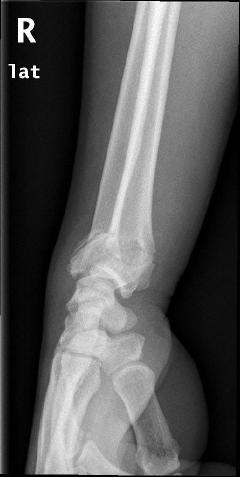

Κατάγματα κάτω πέρατος κερκίδος – κατάγματα Colle’s

Είναι τα συχνότερα κατάγματα στον σκελετό και συμβαίνουν συνήθως σε γυναίκες μετά την εμμηνόπαυση, όταν πέφτουν στο έδαφος και προσπαθούν με συγκρατηθούν βάζοντας την παλάμη. Τα πιο δύσκολα να αντιμετωπιστούν είναι εκείνα που επεκτείνονται μέχρι την αρθρική επιφάνεια.

Περίπτωση 1ου ασθενούς